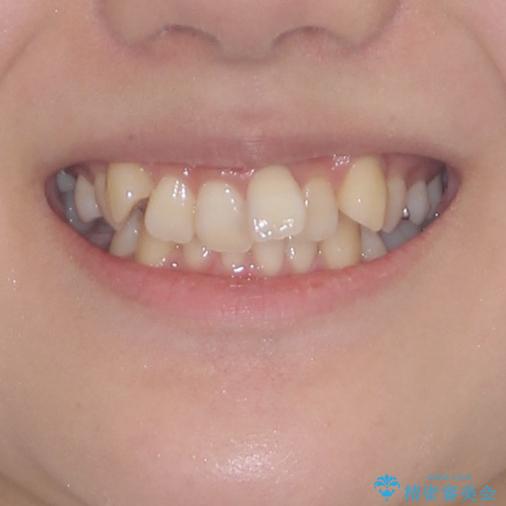

前歯の歯並びを治したい ワイヤー装置での抜歯矯正

- 前歯の叢生と八重歯を気にして来院された患者様です。

叢生が強く、奥歯の咬合も左右差が大きかったため、上下左右4本を抜歯して、ワイヤー矯正を行うこととしました。

20歳前後と年齢が若かったため、非常にスムーズに歯列が整い、1年半をかけずに治療を終えることができました。